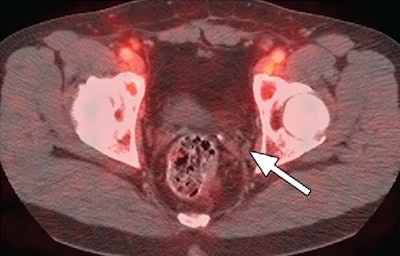

In addition, an Italian study compared FACBC-PET/CT with carbon-11 choline PET/CT for detecting recurrent prostate cancer in 15 patients (Nanni et al, European Journal of Nuclear Medicine and Molecular Imaging, July 2013, Vol. 40:1 Supplement, pp. 11-17).

FACBC-PET/CT had a detection rate of 40% (six positive patients and nine negative patients), compared with 20% (three positive patients and 12 negative patients) for carbon-11 choline. FACBC detected 11 lesions (five bone, five lymph node, and one local relapse), compared with six lesions (four bone, one lymph node, one local relapse) with carbon-11 choline. FACBC detected all six of the carbon-11 choline lesions, and there were no adverse reactions to the agent.